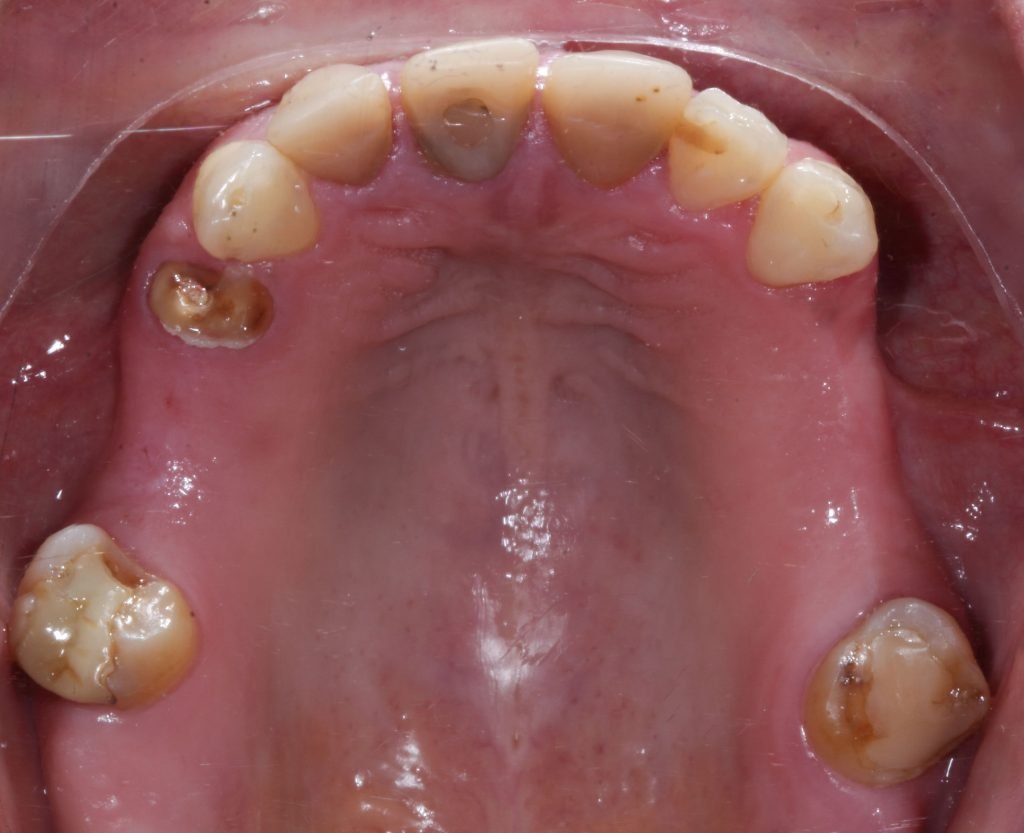

Punto Bajío Casos Clínicos Prótesis Fija sobre Implante unitario Inicio Provisional Final Prótesis Parcial Fija sobre 2 Implantes 2 Implantes Final Prótesis Bucal Removible Inicial Inicial Superior Inicial Inferior Rayos X Inicial Rayos X Inicial Frontal Final Final Superior Final Inferior Prótesis Parcial Fija/ Coronas de Circonio Sonrisa Inicial Foto Inicial Foto Inicial Inferior Foto Final Inferior Foto Final Sonrisa Final Prótesis Total Protesis Inmediatas 1 Protesis Inmediatas 2 Prótesis Removible/ Coronas Metal-Ceramica Carillas Incrustaciones Endodoncia